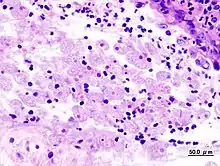

Ces mêmes enzymes permettent aussi de déjouer les défenses immunitaires en clivant des immunoglobulines[19], et en inhibant le chimiotactisme des polynucléaires[11]. L'amibe pathogène se nourrit également des cellules détruites par phagocytose et on voit souvent au microscope des globules rouges à l'intérieur des vacuoles de son cytoplasme[10].

L'examen direct au microscope optique sur plaque chauffante est longtemps restée la méthode de diagnostic la plus répandue dans le monde entier. Cet examen permet de voir les formes végétatives minuta et histolytica en mouvement (sous l'influence de la chaleur), et affirmer E. histolytica avec certitude lors de la mise en évidence de trophozoïtes hématophages[22].

La rectoscopie montre une muqueuse inflammatoire et hémorragique avec des ulcérations « en coup d'ongle ». La biopsie colique peut montrer en phase aigüe les microabcès « en bouton de chemise », et en cas d'amœbome, un granulome inflammatoire.